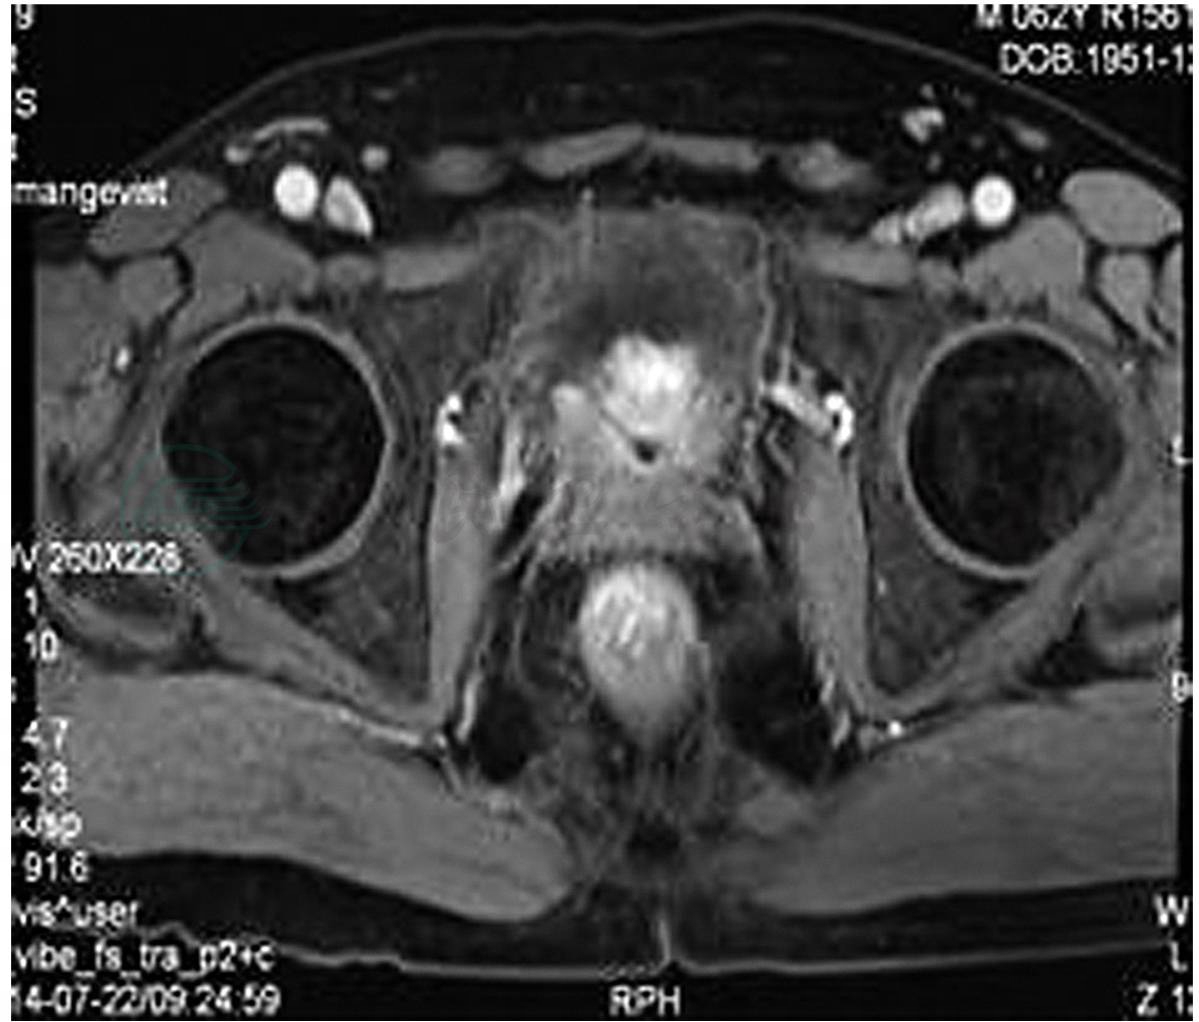

患者男,63岁,因“发现前列腺癌1年,腰痛1周”入院。1年前因排尿困难于我院就诊。TPSA:3.16μg/L。B超提示前列腺增生。直肠指检质地中等硬度,未扪及明显肿块。行经尿道前列腺电切术。术后前列腺常规病理检查提示:前列腺腺癌,Gleason评分5+5=10。免疫组化:PSA部分+,P504S+,34βE12-,P63-,Syn-,CgA-,CD56-。完善骨扫描未见转移灶。行MAB内分泌治疗。定期复查血液TPSA,前列腺磁共振及骨扫描。术后1年因双侧腰胀痛再次就诊入院。B超提示:左侧输尿管下段多发结石伴左肾积水(中度),左肾结石,右肾结晶,右肾集合系统局部分离。前列腺增强磁共振成像(图1):前列腺电切术后,前列腺膀胱交界处结节灶,考虑前列腺癌可能。膀胱后壁增厚多发结节灶,前列腺癌侵犯膀胱,左侧输尿管扩张,其膀胱开口部受侵狭窄。全身骨显像:①T8椎体右侧点状骨代谢轻度活跃,考虑退行变可能;②右11后肋点状局灶性骨代谢轻度活跃灶,骶骨骨代谢不均匀,建议随访。肾动态显像:①右肾血流灌注良好,功能尚可,排泄延缓;②左肾血流灌注差,功能严重受损。

图1 前列腺增强磁共振成像